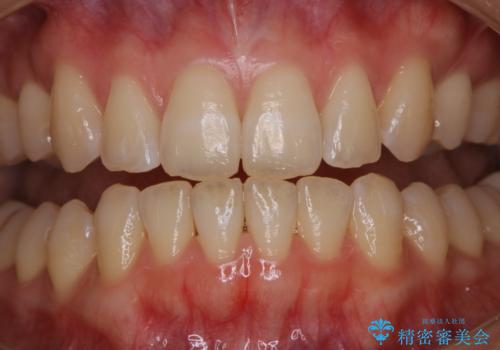

オフィスホワイトニング(エクセレントコース)

- オフィスホワイトニング希望で1日で白くしたいとのことでした。

オフィスホワイトニングのエクセレントコース(¥29700)を行いました。